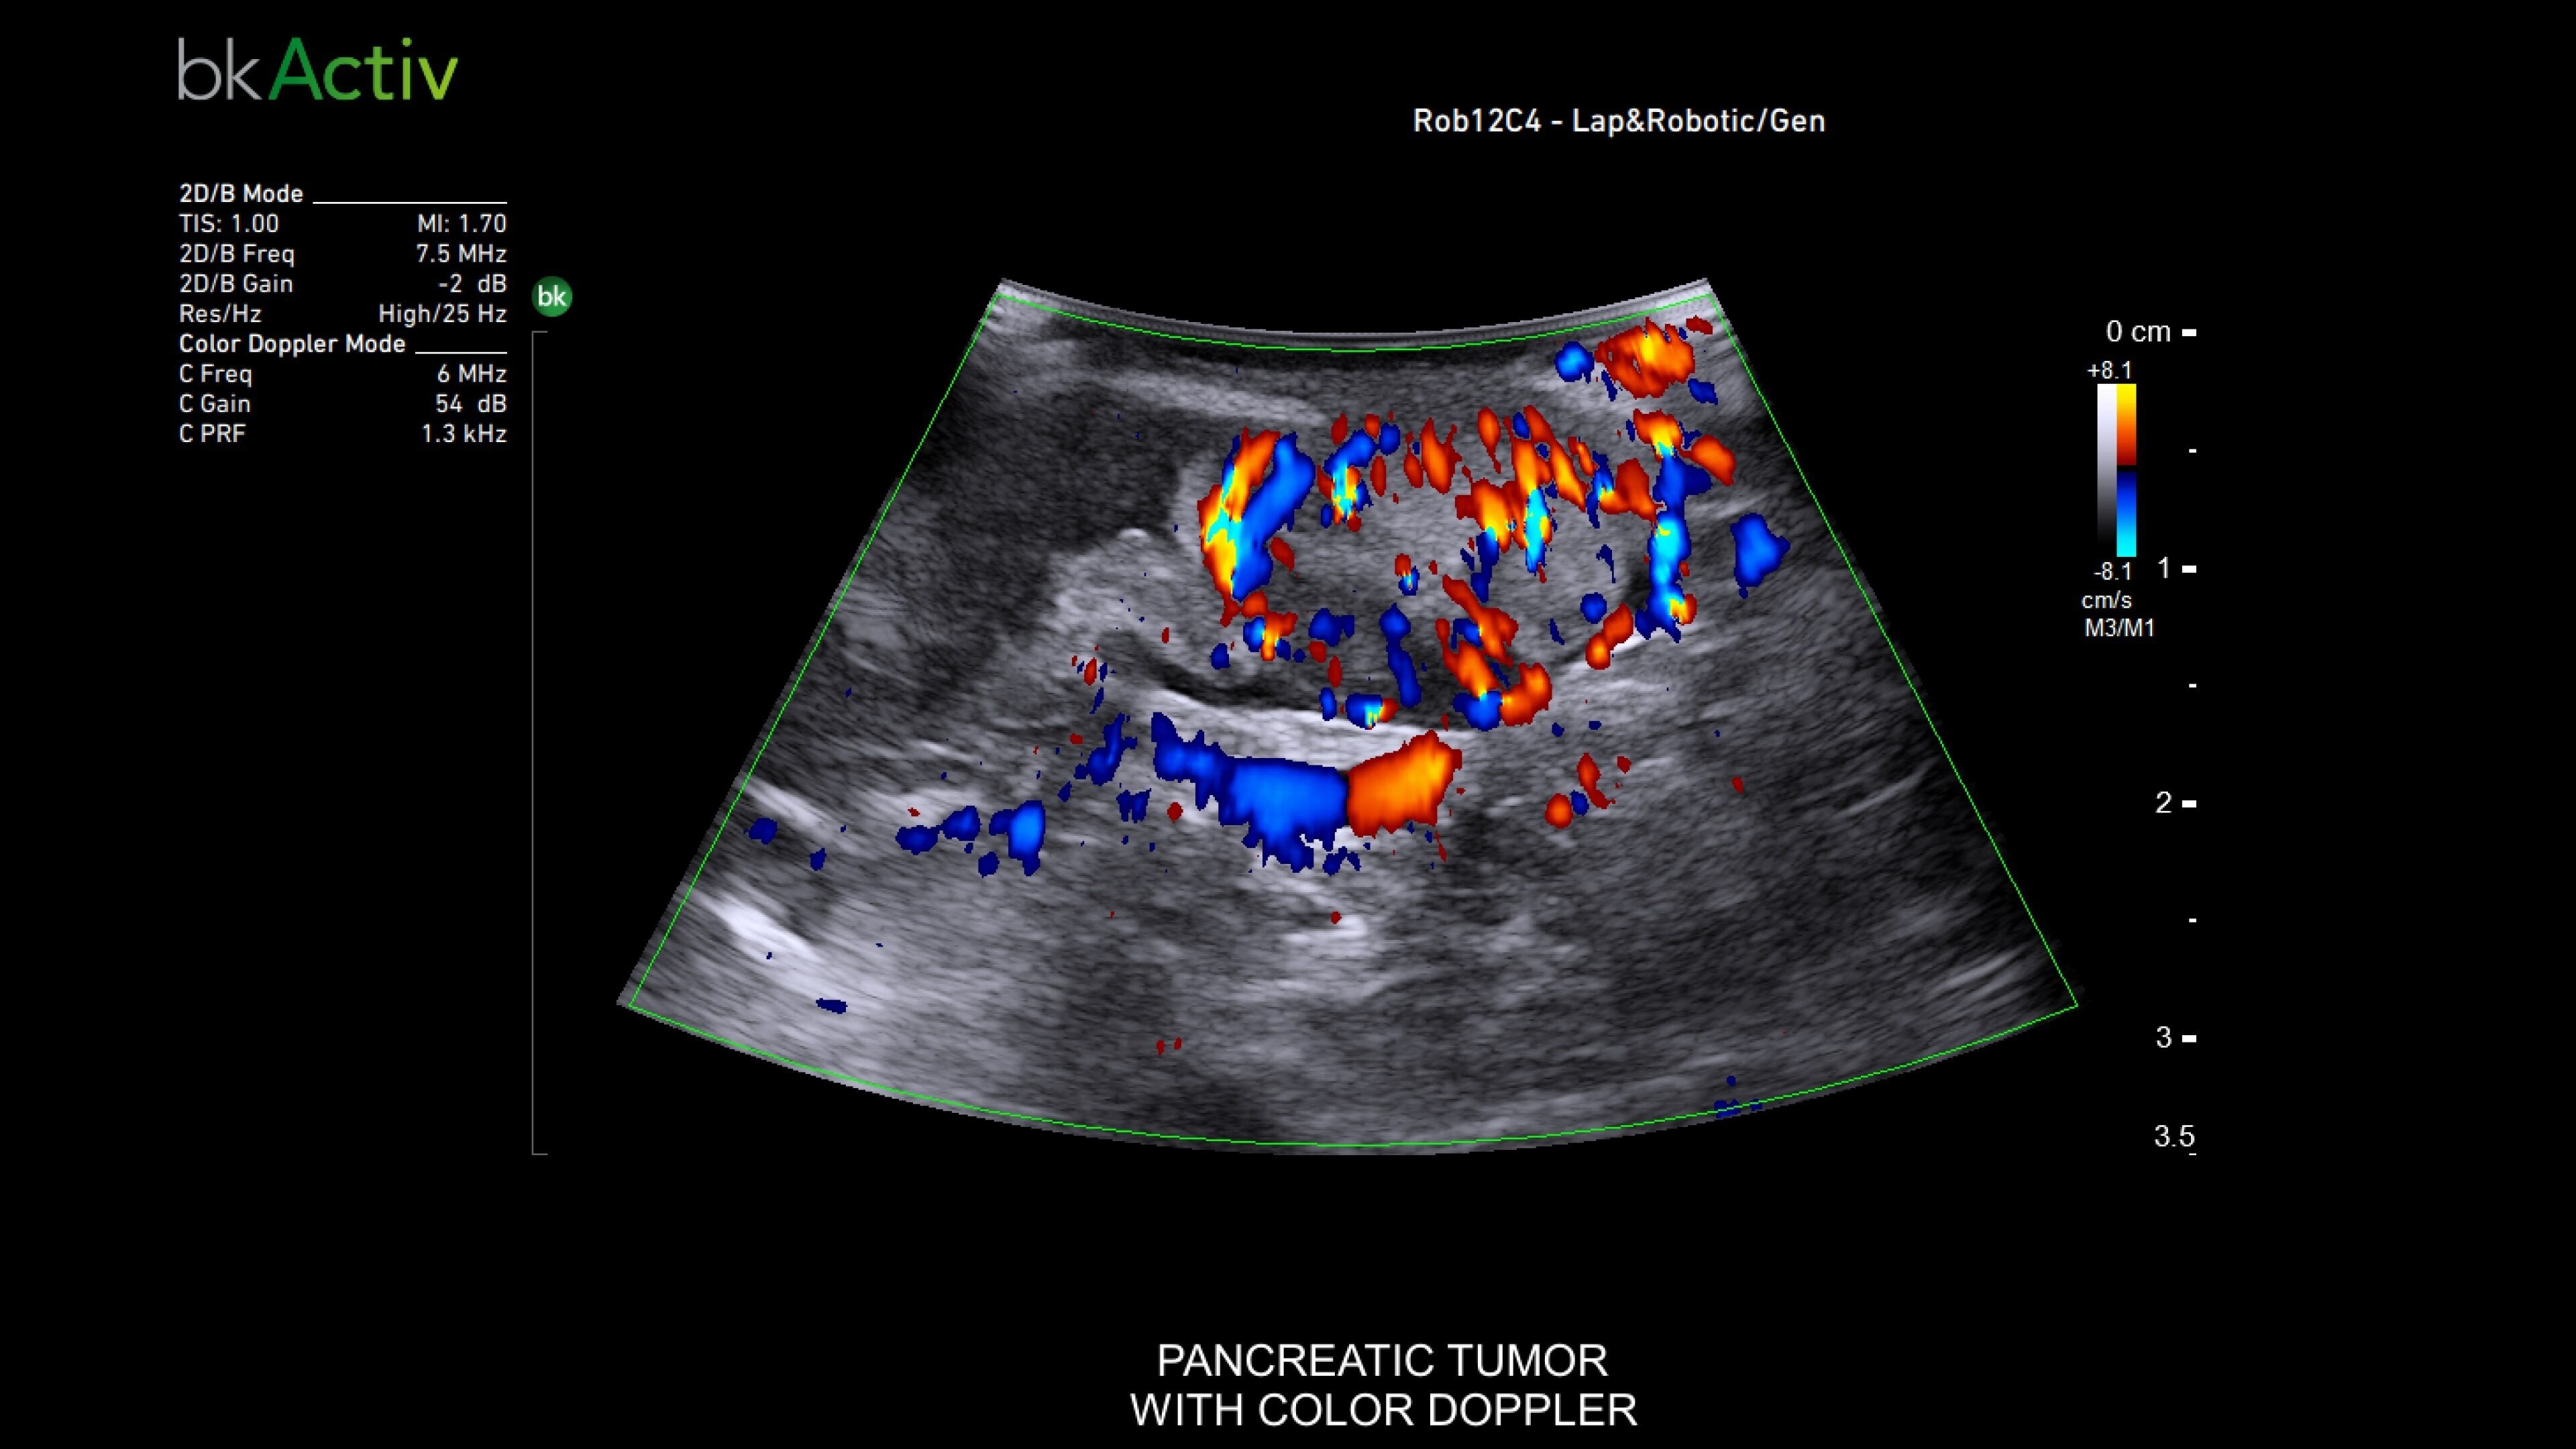

The bkActiv ultrasound system delivers remarkable imaging for general surgery, including anorectal, robotics-assisted, and pelvic floor surgeries. Its advanced algorithms provide uniform image resolution and greater detail, while the remote control allows surgeons to adjust images within the sterile field. For anorectal surgeries, bkActiv offers high-definition imaging to visualize normal and abnormal anatomy, including anal sphincter injuries and rectal cancer. In robotics-assisted surgeries, the system's robotic transducers provide real-time, high-resolution imaging to locate and assess lesions and critical structures. For pelvic floor surgeries, bkActiv's advanced 3D architecture supports dynamic, real-time examination during procedures.